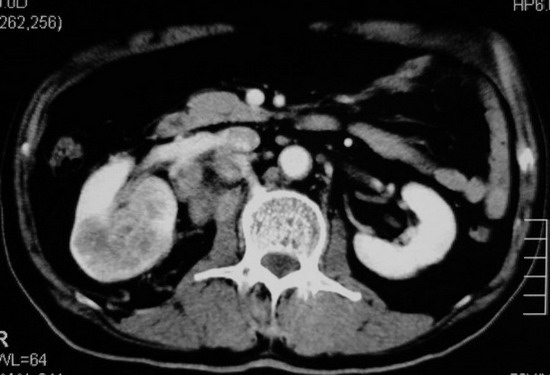

以下是引用杀毒软件在2008-11-17 19:15:00的发言:[br]考虑------右肾癌合并肾静脉---同侧肾上腺受侵可能性大

以下是引用zjzjr在2008-11-17 20:45:00的发言:[br]考虑------右肾癌合并肾静脉---同侧肾上腺受侵可能性大及腹膜后淋巴结转移.